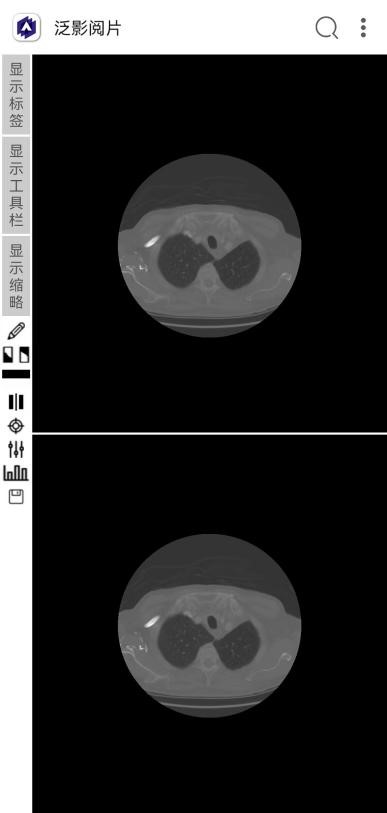

二宫格显示。以两个宫格方式显示2张图像,如下图所示。